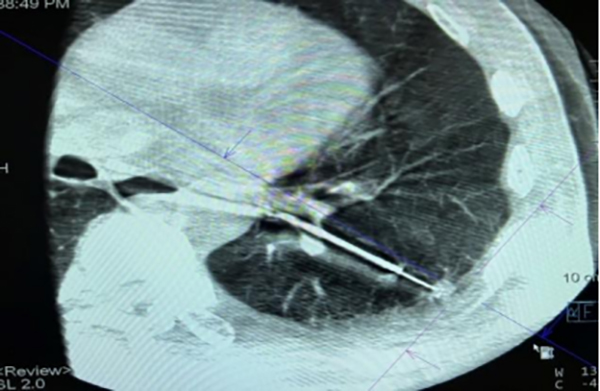

双C臂术中成像引导肺外周结节活检术